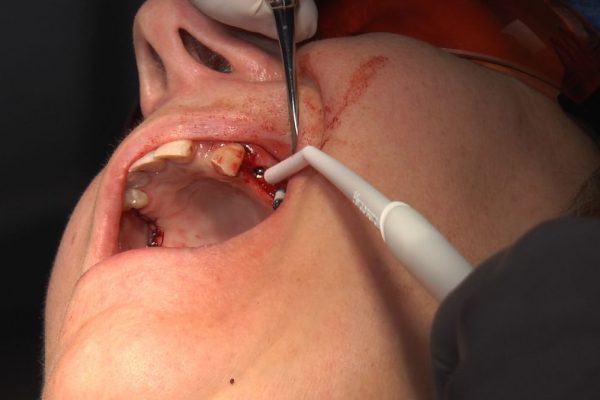

W ostatni weekend czerwca 2018 roku kursanci II Sezonu Preludium Implantologii odbyli piątą, finałową sesję, która w całości podporządkowana była praktyce. W ciągu dwóch dni zabiegowych Lekarze uczestniczący w szkoleniu przeprowadzili szereg zabiegów pod kierunkiem dr n.med. Violetty Szycik. Wszczepili 17 implantów oraz przeprowadzili ekstrakcje i zabiegi regeneracyjne kości. Zabiegi były wykonywane także w sedacji dożylnej z udziałem specjalisty anestezjologii i intensywnej terapii dr Jolanty Grzybowskiej. Preludium implantologii to nowy program edukacyjny dla adeptów implantologii stomatologicznej, którego celem jest wprowadzenie do implantologii poprzez pozyskanie wiedzy w szerokim zakresie i uwzględnieniem szczegółów mających decydujące znaczenie dla powodzenia leczenia implantologicznego. Ale tak jak wszystkie szkolenia w Instytucie Vivadental, w tym wiodące Practiculum Implantologii, zorientowane jest na praktyce i samodzielnym wykonywaniu zabiegów pod kierunkiem Mentora. To najlepsza edukacja w medycynie zabiegowej, a zarazem najlepszy start do implantologii.